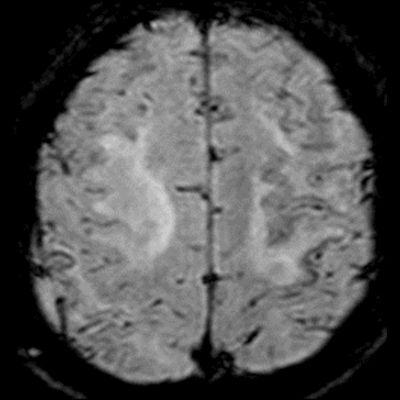

- Bilateral asimetrik subkortikal ve derin beyaz cevherde T1 ağırlıklı görüntülerde belirgin hipointens (oklar), T2A görüntülerde hiperintens (oklar), gri cevhere bakan kesimi düzgün (oklar), DAG’de hiperintens (ok) lezyonlar izlendi. Lezyonlarda T2/FLAIR uyumsuzluğu vardı (ok). Serebellar beyaz cevherde dentat nukleusu koruyan hilal işareti görüldü (ok başı). SWI sekansta sol motor kortekste hipointens kronik glioinflamatuar reaksiyon ile uyumlu sinyal değişikliği izlendi (ok başı).

- Çoğunlukla subkortikal beyaz cevherde ve U fiberlerde, asimetrik, genelde kitle etkisi yapmayan ve kontrastlanmayan demiyelinizan lezyonlar görülür. Korteks ve derin gri cevher tutulumu daha nadirdir.

- PML lezyonları, T1A görüntülerde belirgin hipointenstir. Gri cevhere bakan yüzleri keskin olup T2/FLAIR uyumsuzluğu önemli özelliğidir.